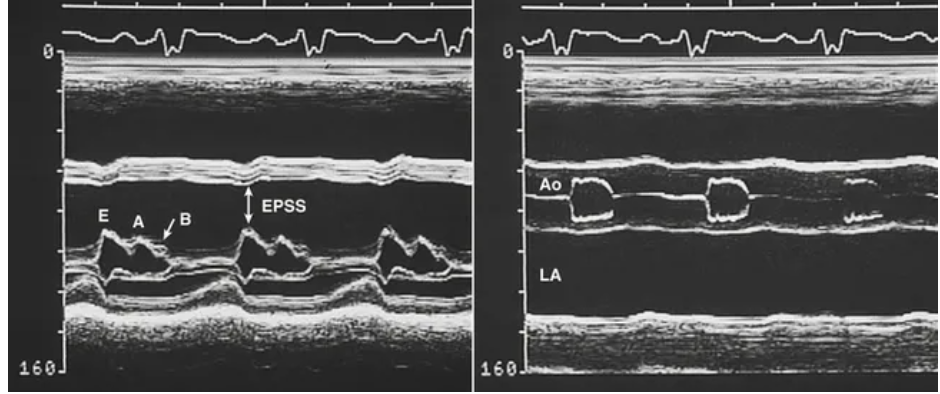

M-mode findings

• thin walls with decreased function

• increased chamber size

• increased EPSS (MV E point to septal separation) > 0.7cm due to LV dilatation and decreased septal function

• decreased D-E excursion

• decreased MV excursion *double diamond shape

• B notch on MV due to increased LVEDP ≥15mmHg

*image

M-mode findings in dilated cardiomyopathy.The mitral M-mode shows increased mitral E-point septal separation (EPSS) and a “B-bump” (left). The aortic M-mode shows decreased aortic root motion with early closure of the aortic valve (right).